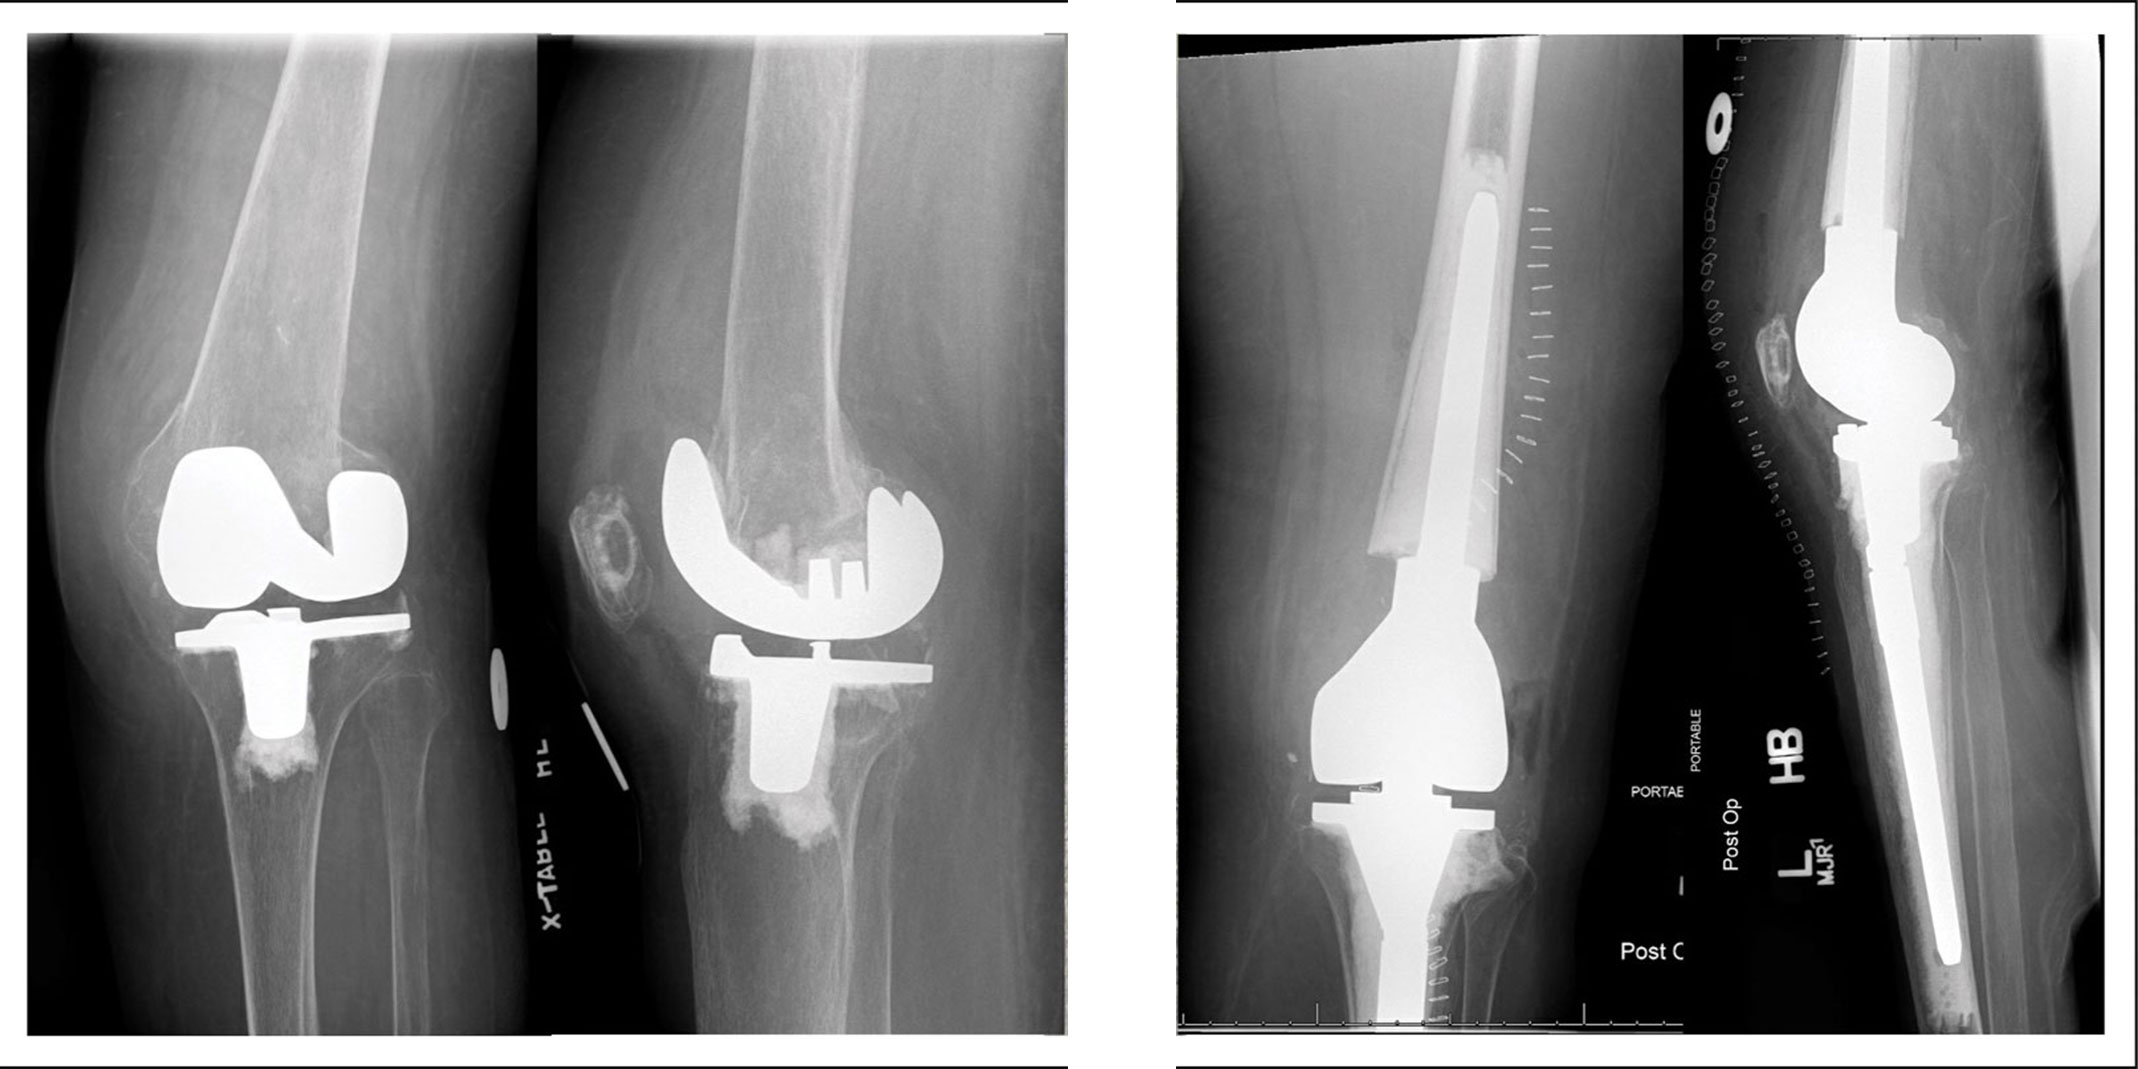

Two different viws (A and B) of a distal comminuted periprosthetic fracture treated with revision total knee replacement (C and D)

Reproduced and adapted from Kuzyk PRT, Watts E, Backstein D. Revision Total Arthroplasty for the Management of Periprosthetic Fractures. J Am Acad Orthop Surg 2017 Sept; 25[9]:624-633.